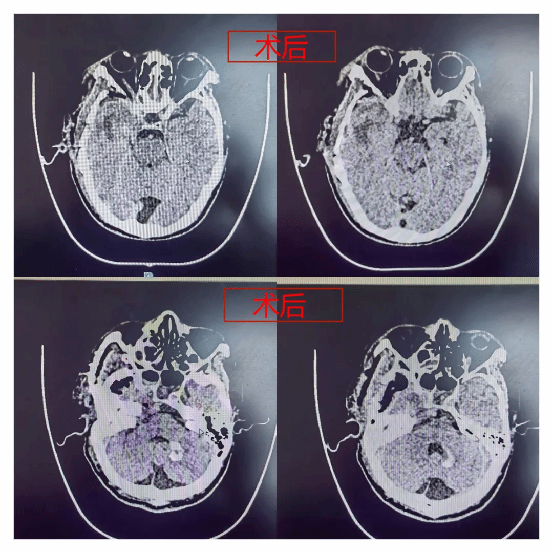

入院后完善了颅脑影像检查,发现右侧桥小脑角区肿瘤已明显挤压脑干。

脑干又称“生命的禁区”,功能受损可能直接影响患者生活质量甚至危及生命安全。经神经外科学科带头人、神经外科二病区主任郭清保详细评估病情,该患者脑干已受压迫,桥小脑角区解剖关系复杂,肿瘤明显挤压脑干及右侧颈内动脉颅内段,同时因患者曾行放疗导致肿瘤与周围组织粘连,分离困难,易出血,手术难度大。

术中,在面对颈内动脉及脑干附着面时郭清保主任谨慎剥离肿物,并时刻关注患者生命体征变化,手术顺利完成。患者术后正常苏醒,神经功能完好保留。